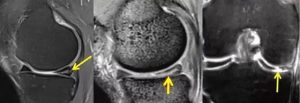

I级- II级可采取保守康复,III级多数建议手术,具体同时根据损伤类型、年龄、活动程度、急慢性损伤?等因素综合判断。

下图III级